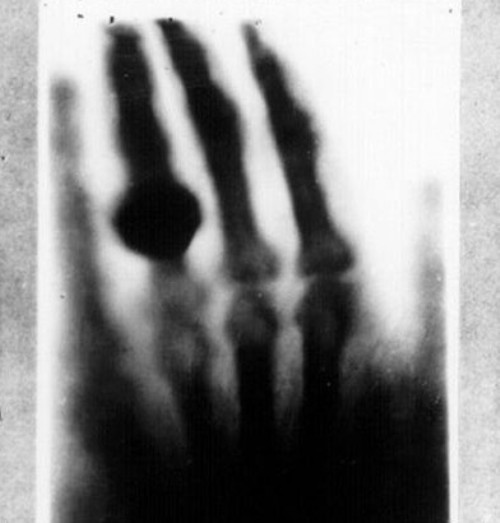

这不是X光片吗?对,没有错,这就是一张X光片,而且是用柯达底片洗印的X光片。1895年,这次轮到德国物理学家伦琴帮助柯达扩大业务了,他无意中发现了X射线,并用柯达胶片记录了下来。第二年,商业嗅觉敏锐的柯达公司进入X光胶片领域,专门开发了一种用于拍摄X光的相纸。